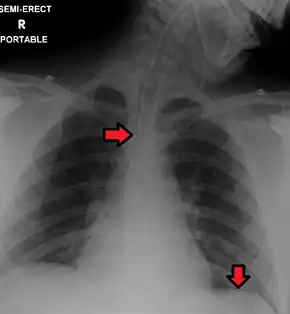

Chest film showing increased opacity in both lungs, indicative of pneumonia